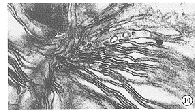

2.3.2 治疗40d血虚证大鼠视网膜超微结构的观察:正常组、预防组:正常光感受器细胞排列整齐,细胞间隙较密,内节线粒体形态结构正常、嵴清楚,外节膜盘结构清楚排列规律整齐(图8、图9)。对照组:视杆锥细胞外节膜盘结构变形、扭曲、肿胀,呈不规则扩散(图10);内节线粒体肿胀,嵴模糊或脱嵴,有的呈空泡状(图11)。小剂量组:视杆锥细胞外节膜盘排列紊乱疏松,部分断裂(图12);内节线粒体肿胀、变大变圆,嵴不清楚(图13)。大剂量组:视杆锥细胞外节膜盘结构变疏松,排列较紊乱(图14);有的内节线粒体肿胀,嵴较清楚(图15)。

图10 对照组外节膜盘结构变形、扭曲、肿胀、空泡,呈不规则扩散 ×28000